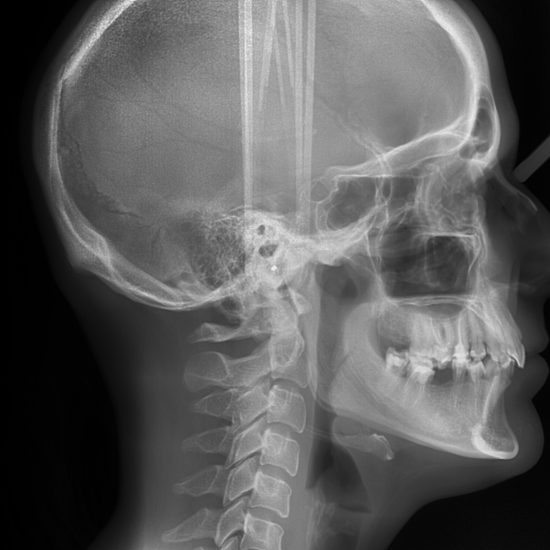

TELERENTGEN

Stranski telerentgenogram ali cepfalostat glave je del morfološke diagnostike v čeljustni in zobni ortopediji. Telerentgenska analiza temelji na stranski sliki glave, na katero se določi mednarodno dogovorjene, dobro ponovljive referenčne točke, ki so na kostnih strukturah, zobeh, mehkih delih glave in obraza. Med točkami se meri razdalje in kote, ki jih označujejo črte.